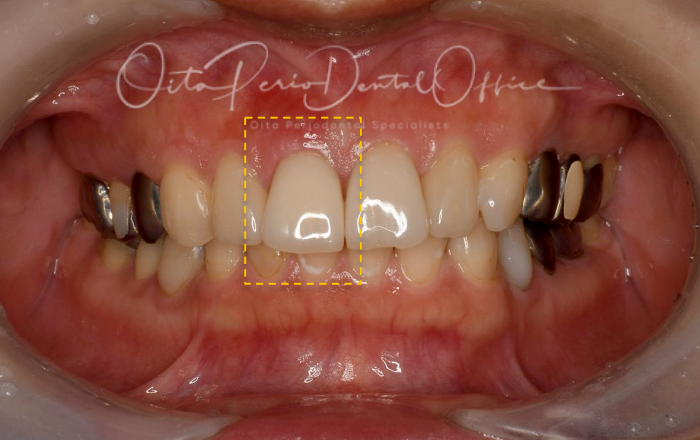

治療前の写真